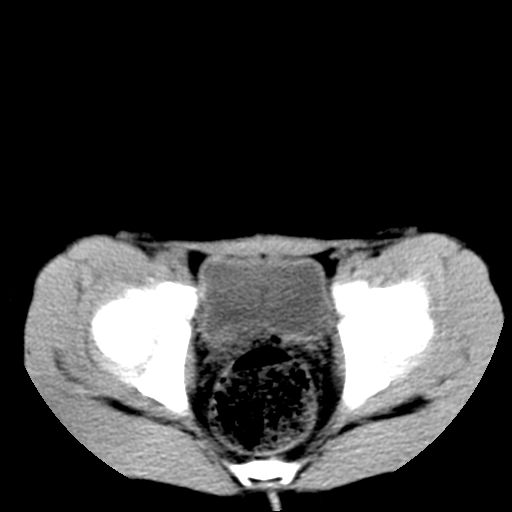

腹部好象未见异常。

腹部ct平扫未见明确异常

腹部ct平扫不能提示哪里有病变。